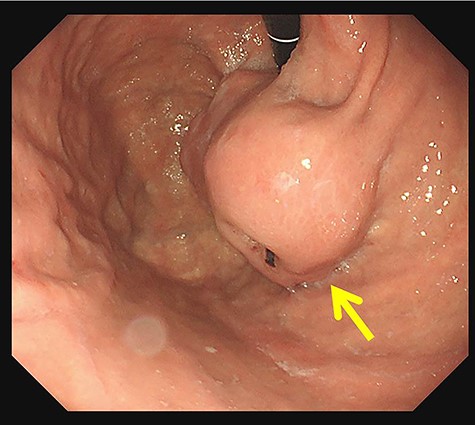

In upper gastrointestinal endoscopy, the tumor looked like a submucosal tumor with delle at the lesser curvature of the cardia (arrow).

On investigating, his hemoglobin was 10 g/dl, and tumor markers, carcinoembryonic antigen and carbohydrate antigen 19-9 (CA 19-9), were elevated to 12.5 ng/ml and 94.3 U/ml, respectively. Tests for Hepatitis B and C viruses were negative. His upper GI endoscopy showed SMT with delle at the lesser curvature of the cardia (Fig. 1). A computed tomography (CT) showed a slightly low-density tumor of 70 mm in diameter at the cardia (Fig. 2). It appeared to infiltrate into the liver directly. We diagnosed it as gastric SMT (suspected GI stromal tumor) with liver infiltration.